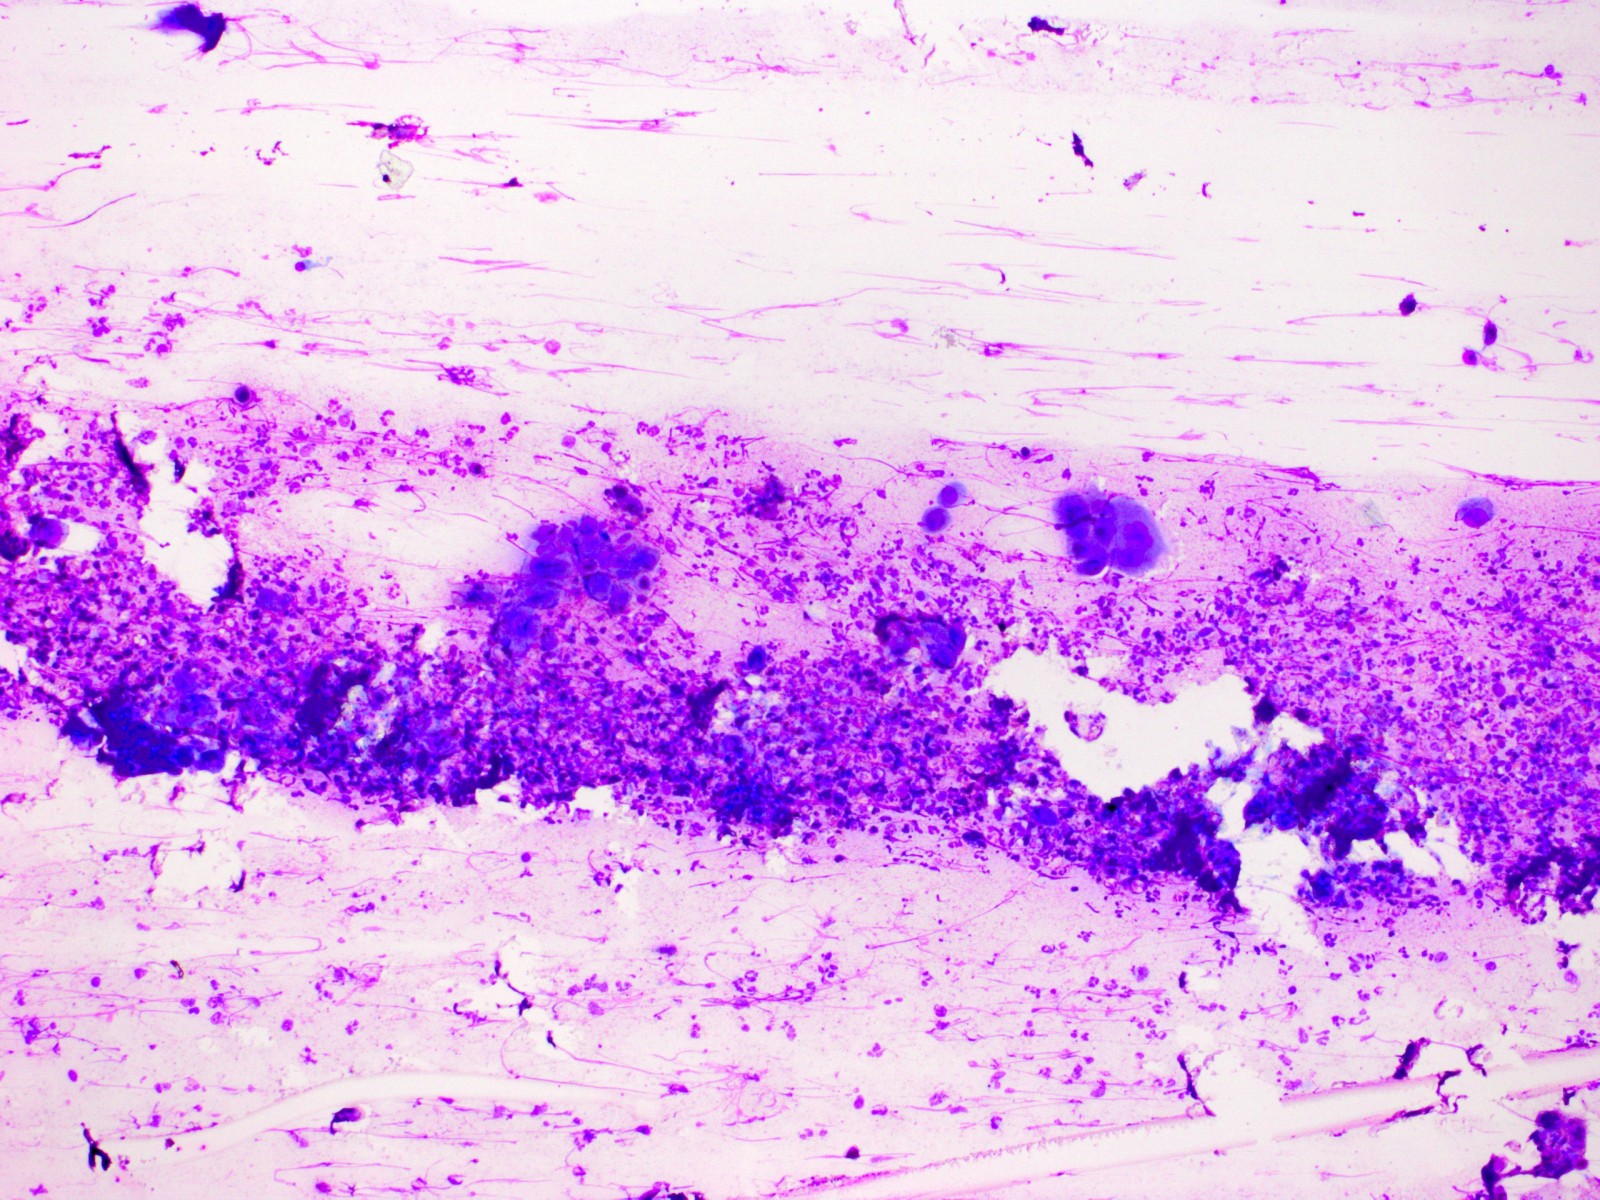

De Tzanck reuscellen hebben in het Diff-Quick preparaat een lichtblauw (basofiel)

cytoplasma en een homogene donkerblauwe of paarse kern (hyperchromatisch, sterk

aankleurend), en zijn zeer groot, veel groter dan een granulocyt. Het zijn geen

macrofagen of Langhanse reuscellen, het zijn conglomeraten van grote epitheliale

cellen (keratinocyten). Er kunnen in het preparaat ook losse van deze grote

hyperchromatische epitheelcellen liggen, maar diagnostisch is het vinden van

een klompje waarbij het cytoplasma samengesmolten is en de kernen tegen elkaar

aanliggen. Losliggende grote afgeronde epitheelcellen (Tzanck cells) kunnen

![Tzanck test met multinucleate giant cells (click on photo to enlarge) [source: www.huidziekten.nl] Tzanck test met multinucleate giant cells](../../../images/soa/Tzanck-test-3z.jpg) |

| Tzanck

test |